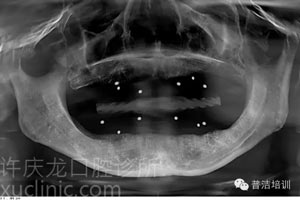

![]() |

上頜傾斜設(shè)計(jì)、下頜應(yīng)用短植體X光 |

總結(jié):此案例是典型的全口無牙伴重度骨萎縮病例。患者就診前已經(jīng)對種植牙的相關(guān)資訊了解很多,除了對功能和美學(xué)要求較高外,還要求治療過程中盡量減少痛苦。我們在上頜后牙采用了種植體傾斜植入設(shè)計(jì),下頜后牙應(yīng)用短植體,從而避免了骨移植手術(shù)。同時(shí)應(yīng)用了電腦導(dǎo)航微創(chuàng)種植技術(shù),在保障最終修復(fù)效果的同時(shí)將創(chuàng)傷降至最低。患者全程并沒有感覺明顯痛苦,對最終的修復(fù)效果也非常滿意。牙科技藝發(fā)展日新月異,我們必將緊跟時(shí)代,我們一直相信現(xiàn)代科技的力量。